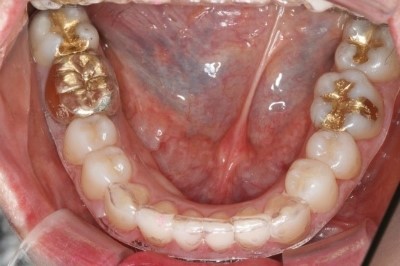

다음은 구강 촬영 사진입니다, X레이보다 확연하게

아랫니의 틀어짐이 보이실 겁니다.